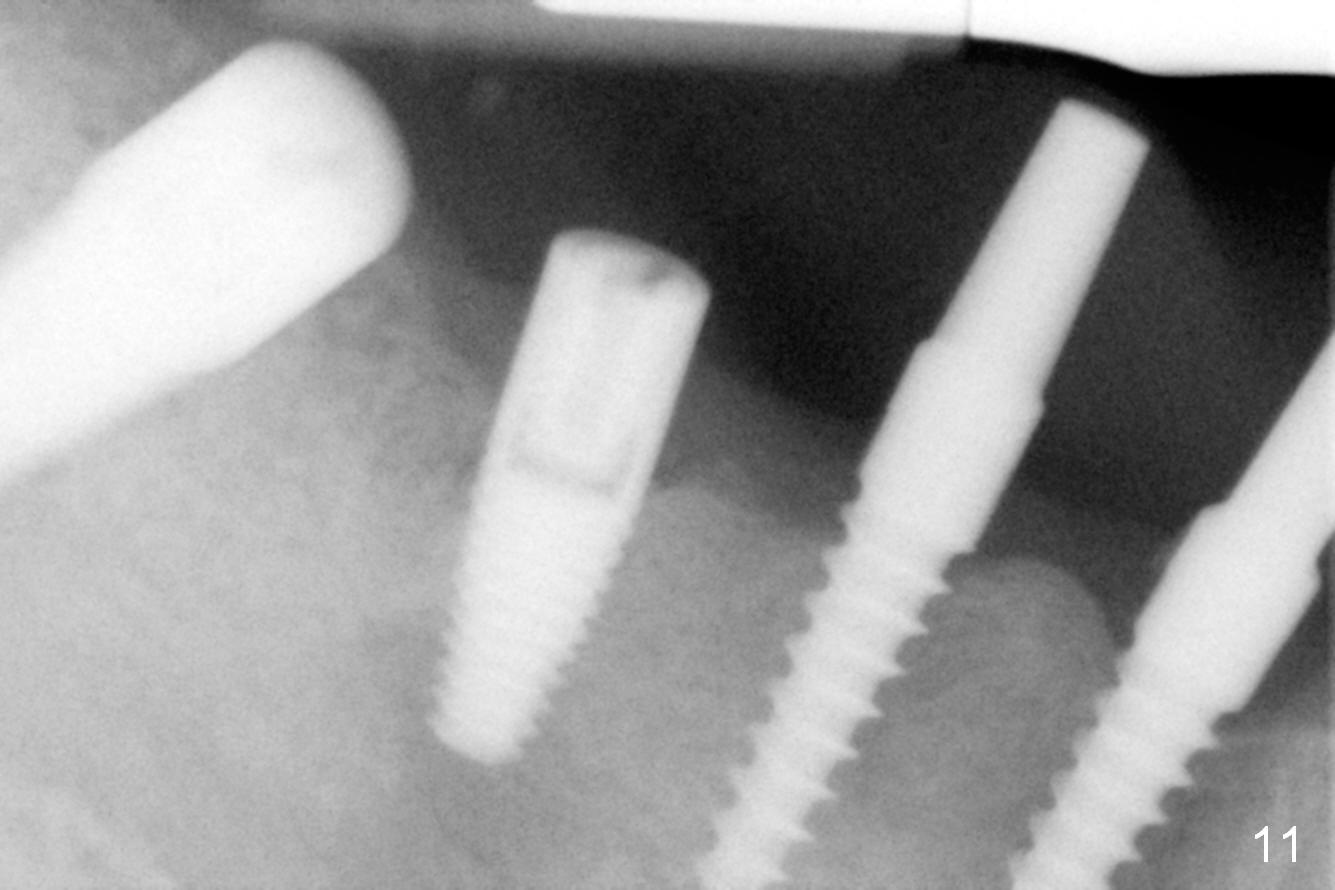

The lower right bridge (from canine (Fig.2: 3) to 1st molar (Fig.1: 6)) fails while a 77-year-old man is undergoing chemotherapy for urinary bladder cancer. The abutments of the bridge are extracted without plan for implants (Fig.4). Four months later, the patient returns for implants (Fig.3), but the ridge is narrow (Fig.5). While 2 of 3x14 mm 1-piece implant are placed at the canine and 1st bicuspid sites, 2 piece ones at the 2nd bicuspid and 1st molar sites (Fig.6: 3.5x11 mm, 5x14 mm). Soft (Fig.7-10) and hard (Fig.11) tissues heal 1 week (Fig.7) and 4 months (Fig.8-11). There is minimal bone resorption 1 year 7 months post cementation (Fig.12,13, non-splinting). It appears that narrow diameter implants are a valid solution to narrow ridge at the sites of the lower canine and premolar. As long as there are enough implants for function, the crowns are not necessary to be splinted. Surprisingly, the patient starts flossing after implant restoration. Retrospectively an immediate provisional bridge should have been fabricated.